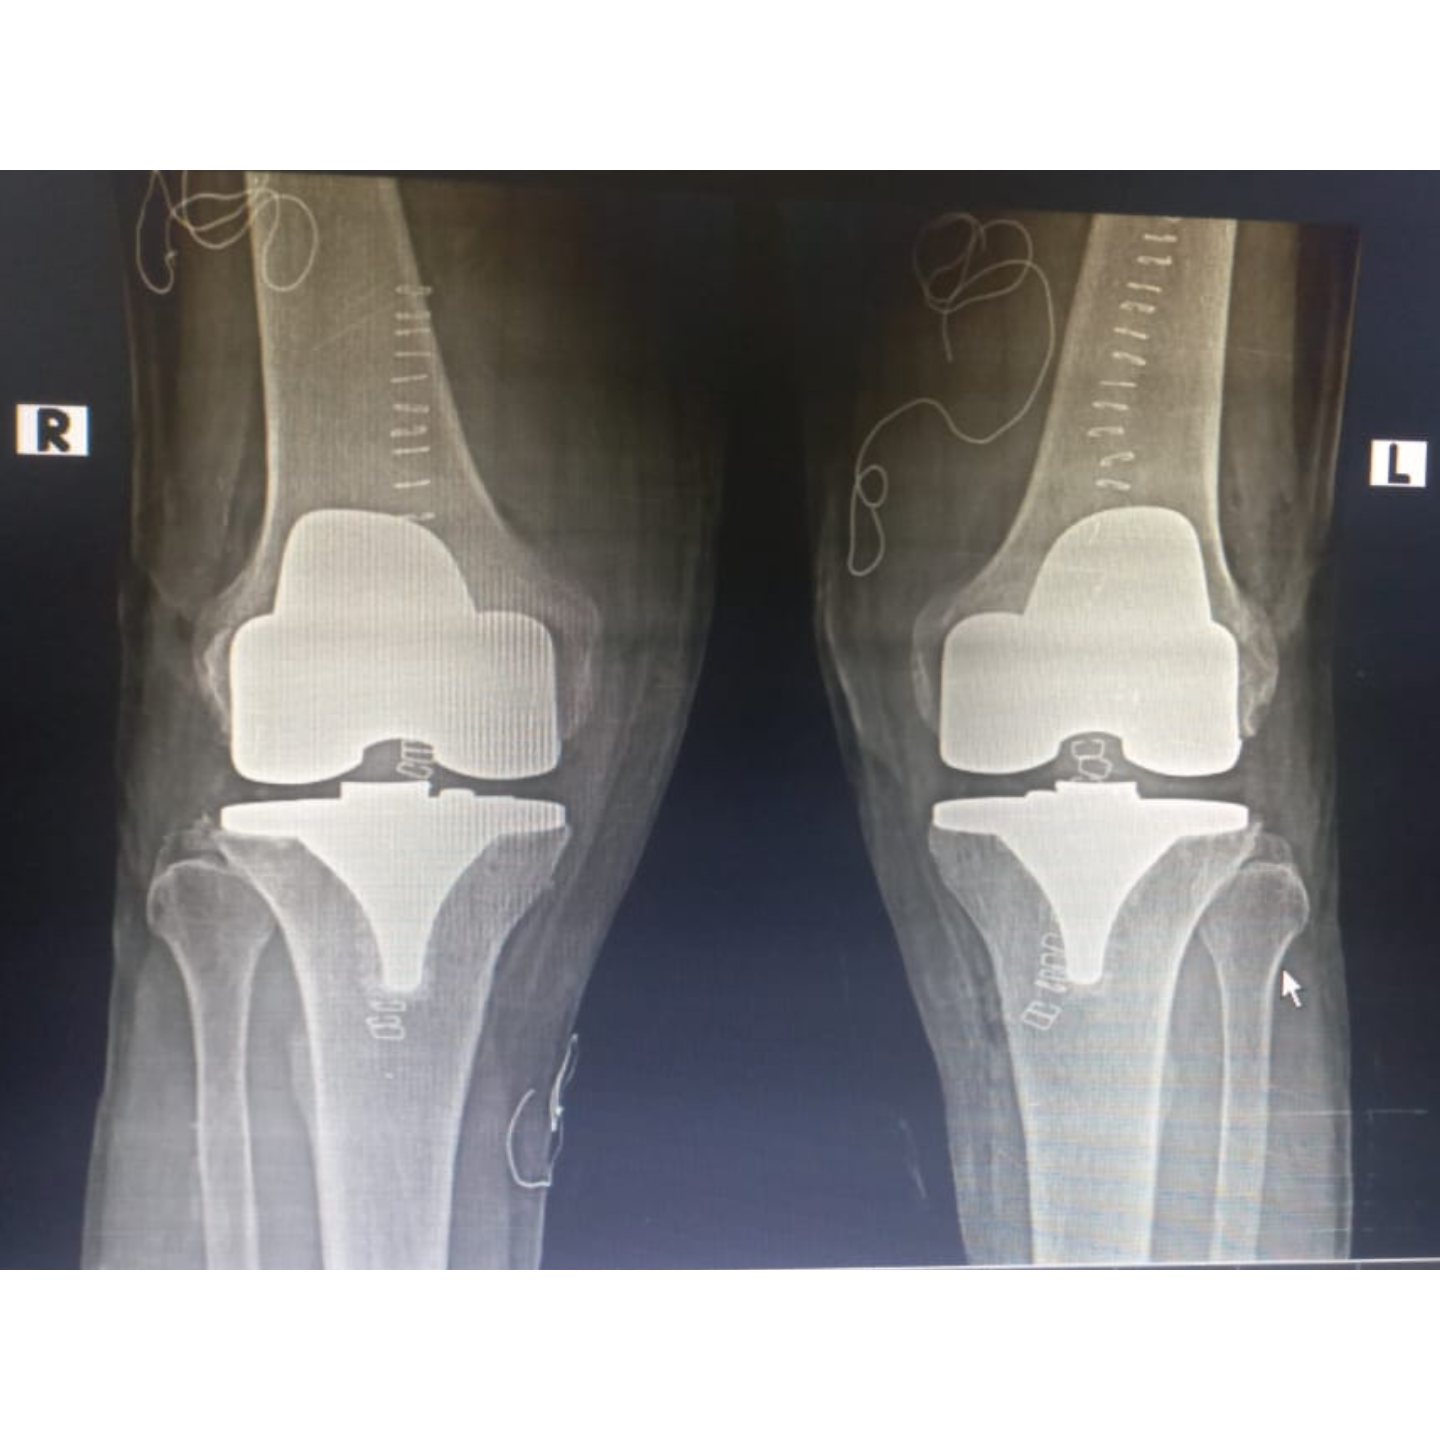

Bilateral total knee replacement